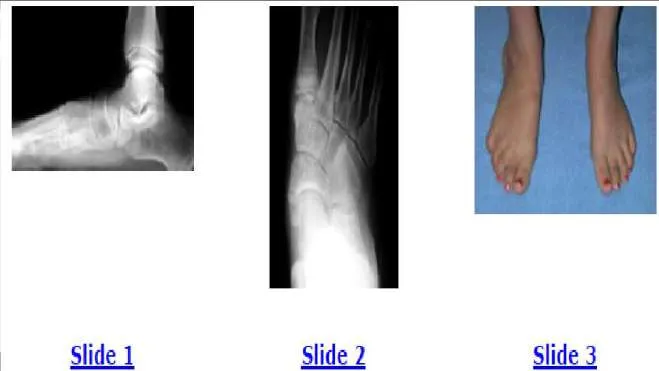

An 11-year-old girl presents with chronic foot pain. Her mother notes that her daughter has had flatfeet since birth, but the condition is worsening. The patient has aching in her foot, the arch of her foot, and her leg with walking and activities. She has been treated for 3 years with various orthotic arch supports. The foot is mobile and flexible on examination. Radiographs (Slide 1 and Slide 2) and a photograph (Slide 3) of her foot are presented. Which of the following surgical treatment alternatives is unacceptable in this patient:

Options:

- Excision of an accessory navicular

- Subtalar arthroerisis

- Excision of a middle facet tarsal coalition

- Medial calcaneus osteotomy

- Lateral column lengthening osteotomy of the calcaneus

Correct Answer: Excision of an accessory navicular

Explanation:

This patient has a flexible flatfoot deformity associated with a painful accessory navicular. No clinical or radiographic findings of a tarsal coalition are present. In addition to excision of the accessory navicular and advancement of the posterior tibial tendon, either a subtalar arthroerisis or an osteotomy of the calcaneus may be necessary.C orrect Answer: Excision of a middle facet tarsal coalition